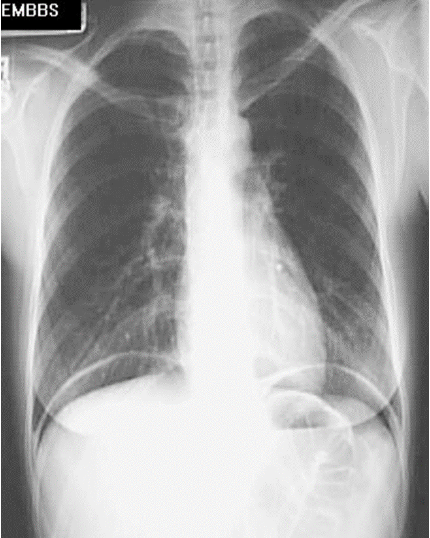

- The best radiograph view to detect pneumoperitoneum is erect chest film. It appears as crescentic area of lucency under diaphragm.

Free gas in the peritoneal cavity:

On this chest radiographs, air can be seen under the domes of both hemidiaphragms.